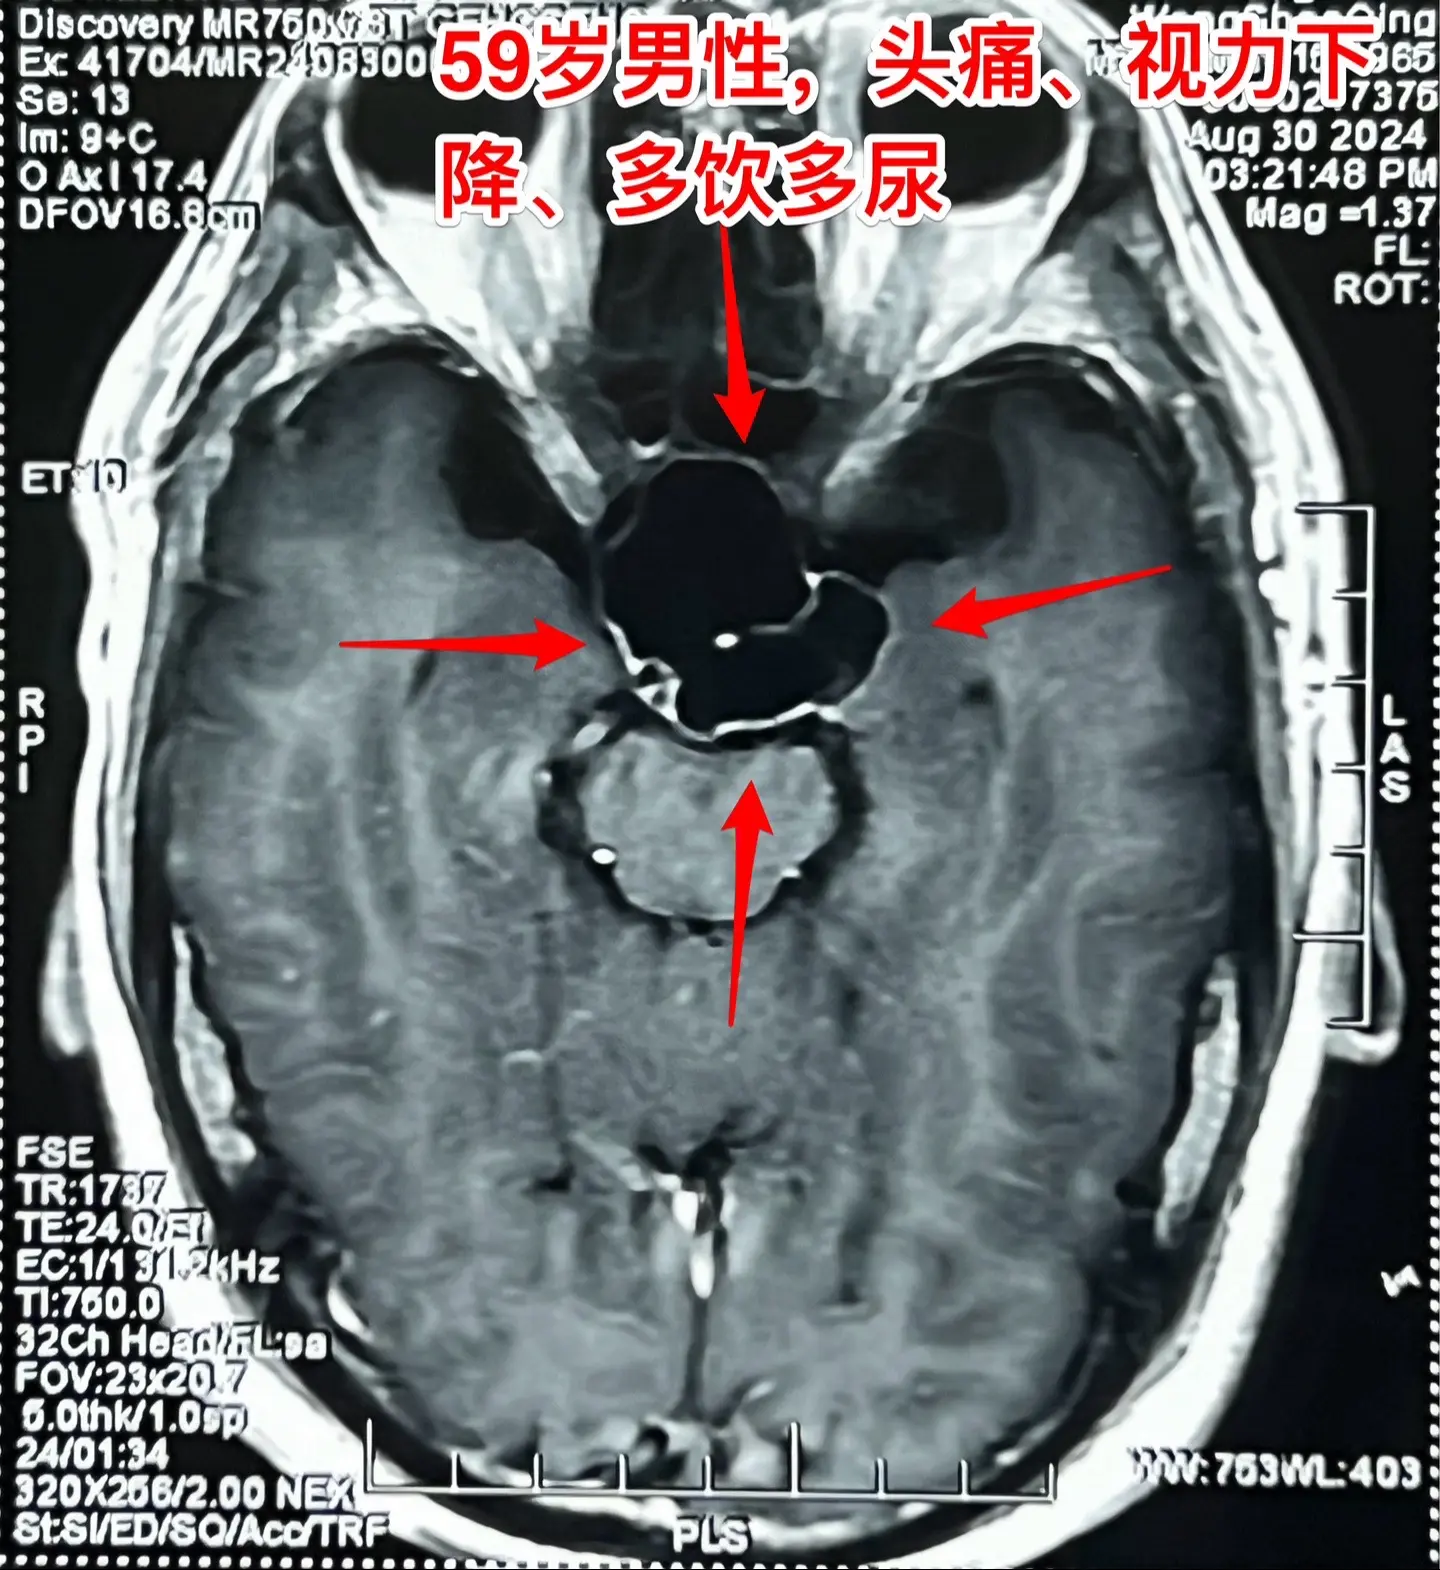

头痛、视力下降、多饮多尿、体重下降。59岁洛阳市男性,近三年感头痛,近一年半感觉视力下降,以为是老花眼,未就医。近9个月多饮多尿,夜间睡眠很差,白天精神很差。近半年体重下降25斤。 2024.8.23到医院就诊,作头部磁共振发现颅咽管瘤。2024.9.5在我科行开颅手术切除颅咽管瘤。手术中发现肿瘤是囊性的,内壁有瘤结节,没有钙化,所以是乳头型颅咽管瘤,肿瘤得到完全切除。手术后双眼视力显著改善。(今年的第133例颅咽管瘤)